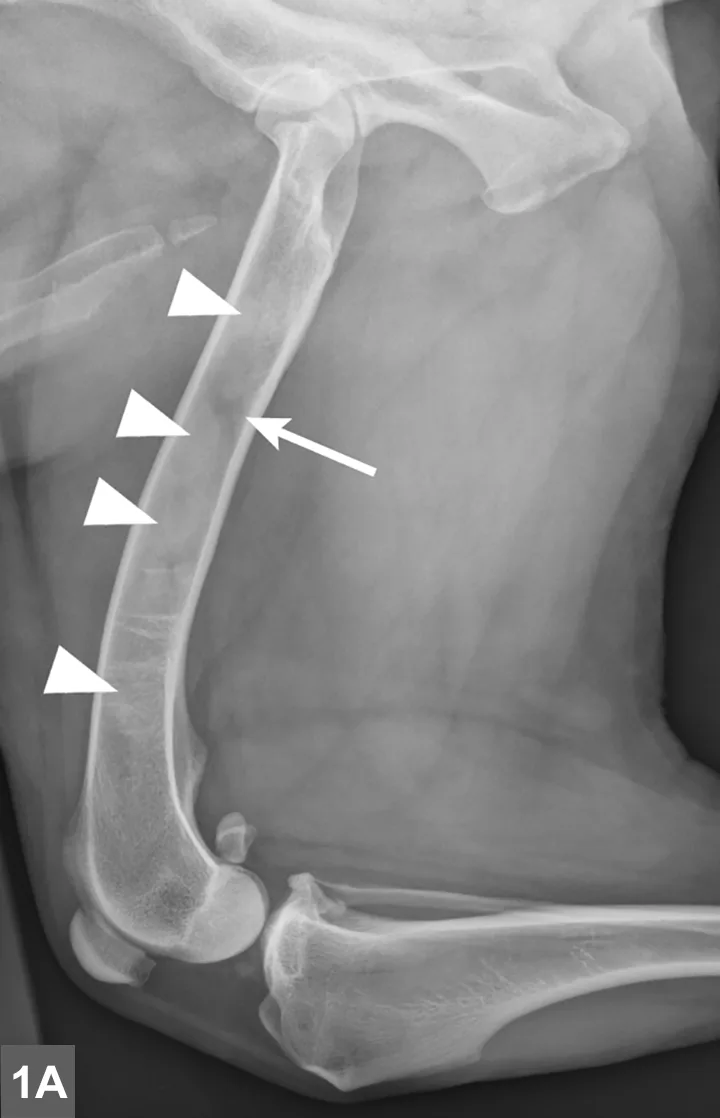

Radiographic signs of panosteitis frequently lag days to weeks behind clinical signs.1,3 The earliest radiographic sign of panosteitis is a decrease in opacity around the nutrient foramen. Later signs include an increase in mineral opacity within the medullary canal of long bones and loss of the normal trabecular bone pattern (Figure 1). Smooth periosteal and endosteal new bone may also be seen in more severe cases (Figure 2). Radiographs of the affected limb may be compared with those of the contralateral limb to assist in diagnosis. Nuclear scintigraphy may assist in diagnosis in cases in which radiographic changes have not yet developed.4

Lateral radiographic projections of the femur (A) and ulna (B, next slide) in dogs with early signs of panosteitis. Note the radiolucency around the nutrient foramen (arrows) and increased opacity within the medullary canal (arrowheads) in both cases.